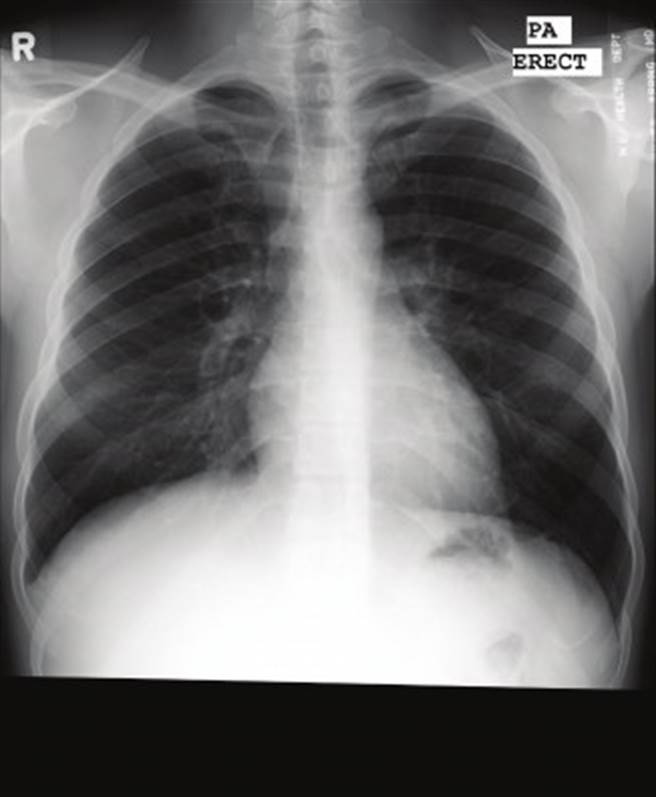

正常未染疫的肺部。(圖/翻攝自柯世祐臉書)

柯世祐醫師今稍早在個人臉書發文,分享兩張X光片表示,一名近70歲的男性有咳嗽症狀,並伴隨呼吸急促、喘,該男子因有萬華接觸史,家人趕緊將他送至醫院急診,醫護人員隨即幫其做檢查,並照X光,發現肺部呈現大片白色,必須馬上插管治療。